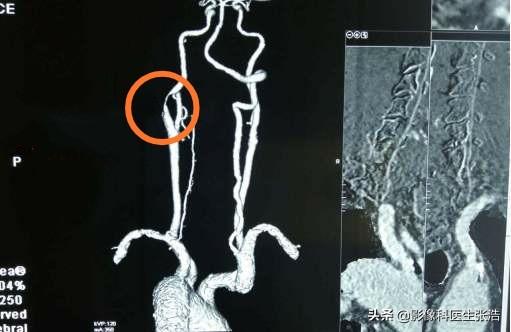

上の頸部のCTA血管造影は、右内頸動脈の限局性狭窄を示す。